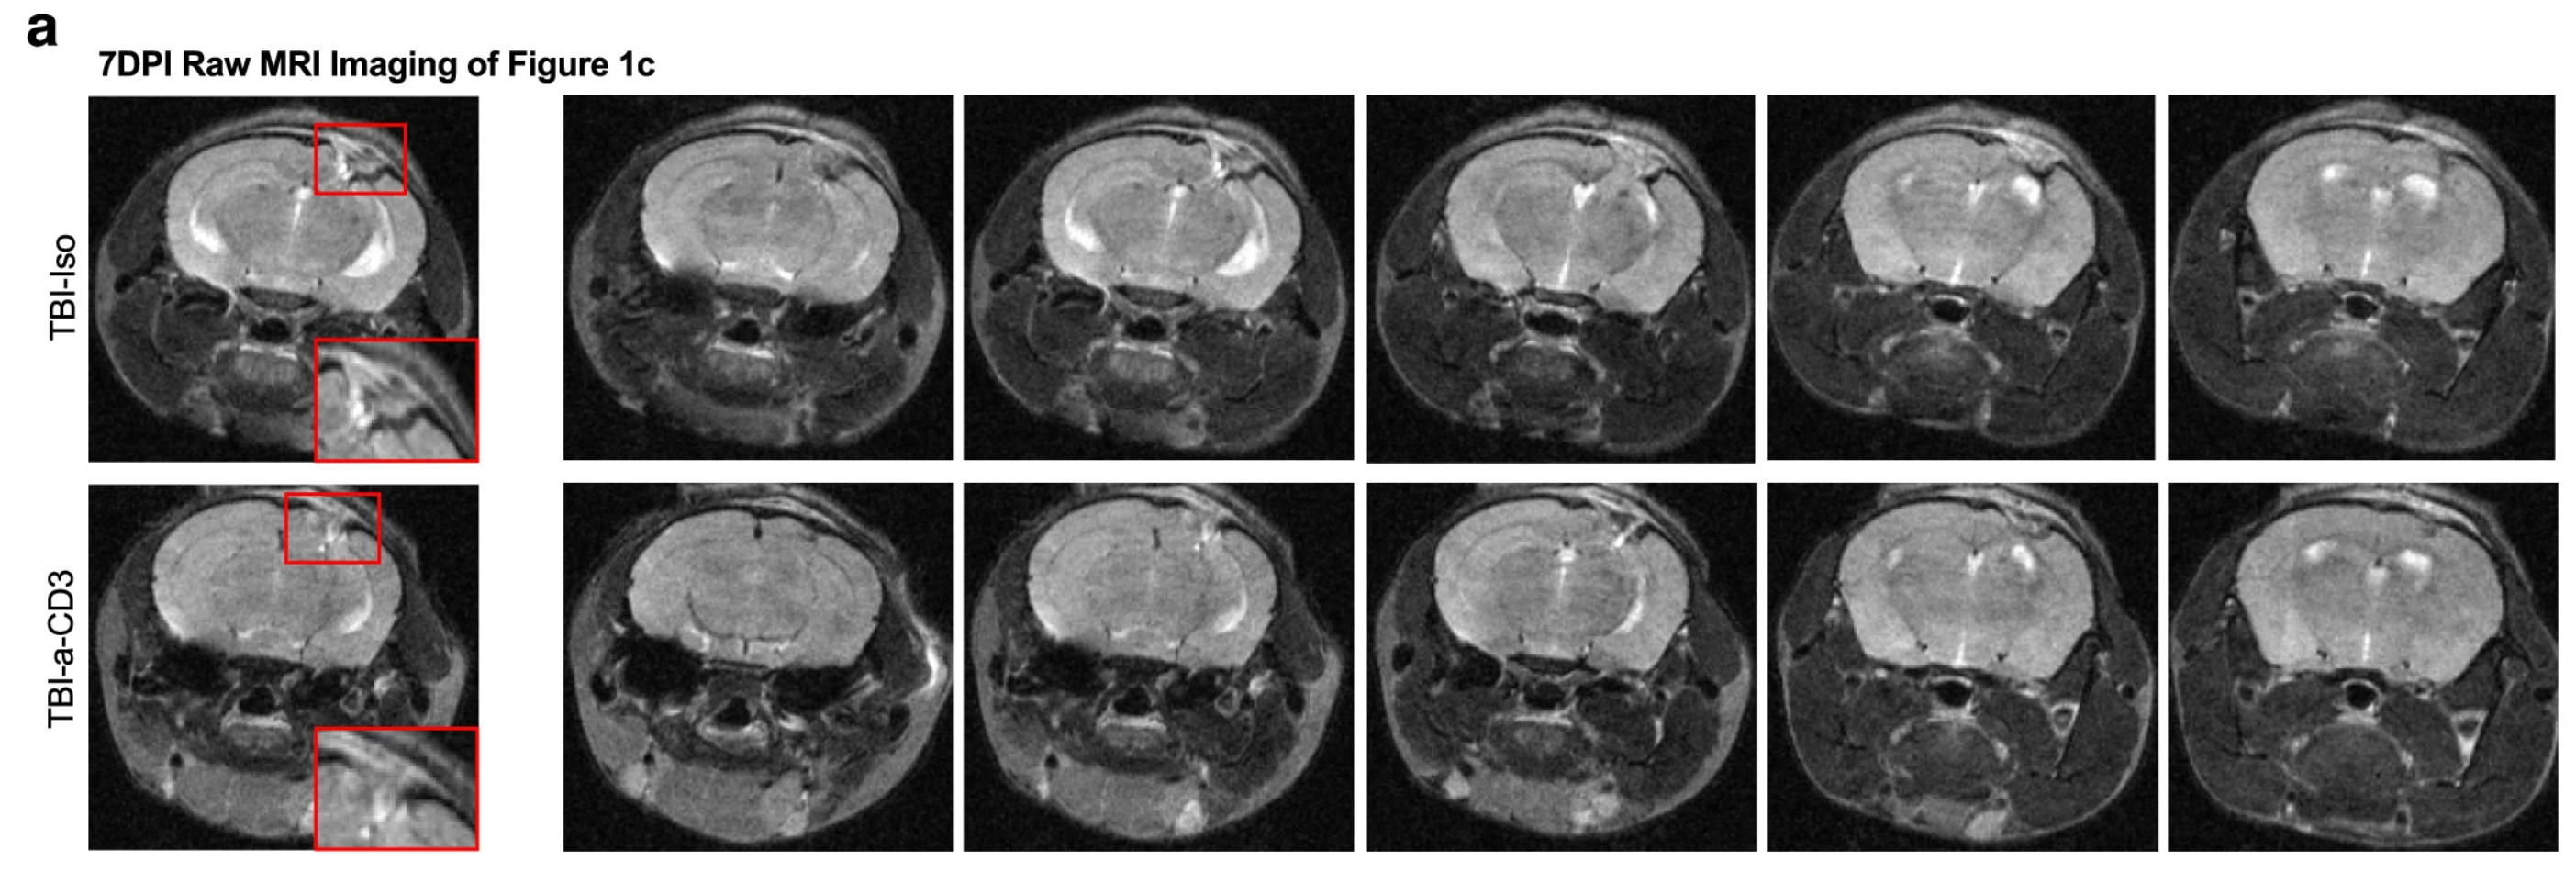

Researchers at Mass General Brigham have developed a nasal spray using an anti-CD3 monoclonal antibody (aCD3 mAb) to stimulate Treg cells. Previous studies show this method successfully reduces inflammation in multiple sclerosis and Alzheimer’s disease models. Now, the team has tested its effects in a mouse model of TBI.

The team tested the nasal treatment in mice with moderate-to-severe TBI. Results showed a significant reduction in brain inflammation, improved motor function, and decreased anxiety-like behavior.

The nasal spray appeared to alter immune signaling between Treg cells and microglia, shifting the immune response from harmful inflammation to tissue repair.